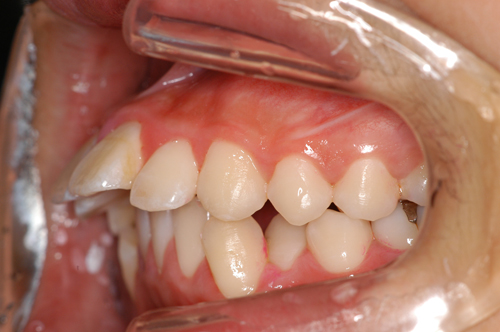

患者:14歳8ヶ月 男性

抜歯部位:上顎、第一小臼歯 下顎第二小臼歯

動的治療期間:18ヶ月